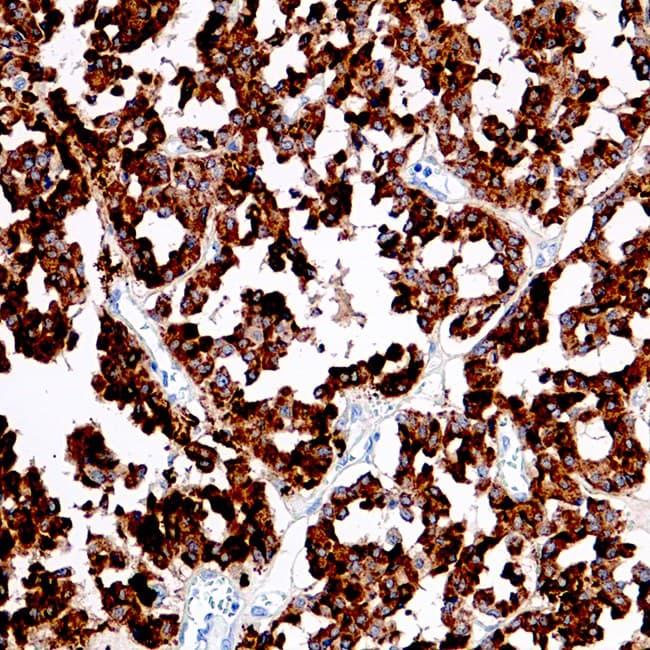

Coupe de carcinome médullaire de la thyroïde

Coupe de carcinome médullaire de la thyroïde